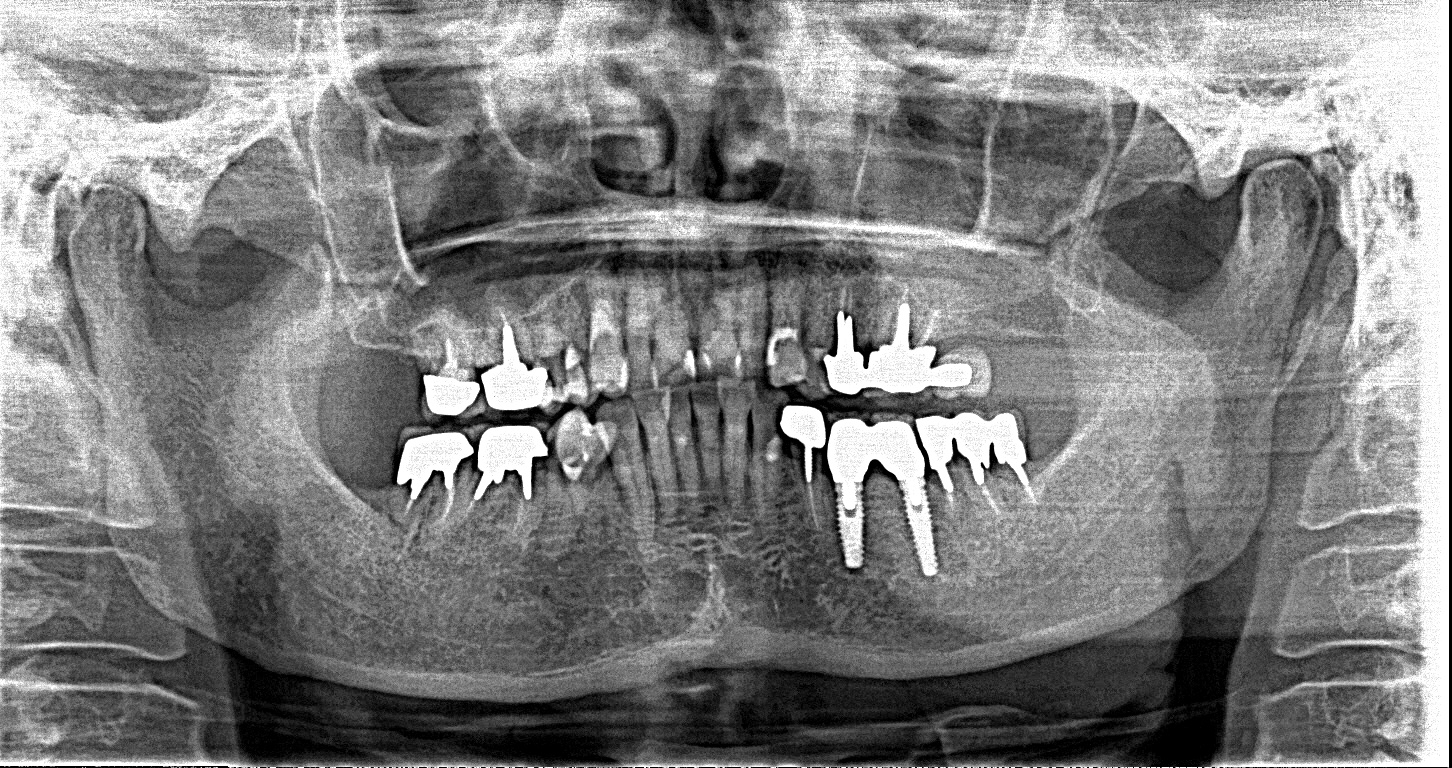

この患者様は、右上の奥歯の歯茎から出血してくるとのことで来院されました。歯周組織検査とレントゲンで診断を行った結果、重度の歯槽膿漏が認められ、保存不可能の為、抜歯になると伝えたところ、入れ歯は絶対に嫌だと言われたので、インプラント治療となりました。CT撮影を行ったところ、上顎洞底までの距離が3ミリ程度しかなかったのですが、骨が固く、フィクスチャーの一次固定が良好だったので、開窓法による上顎洞底挙上術とフィクスチャーの埋入を同時に行いました。約10カ月後に二次手術を行い、上部構造をセットしました。また、右下の臼歯部のブリッジにも大きな二次カリエスが認められ、7番の遠心根が抜歯になり、6番、7番にインプラント治療をしました。